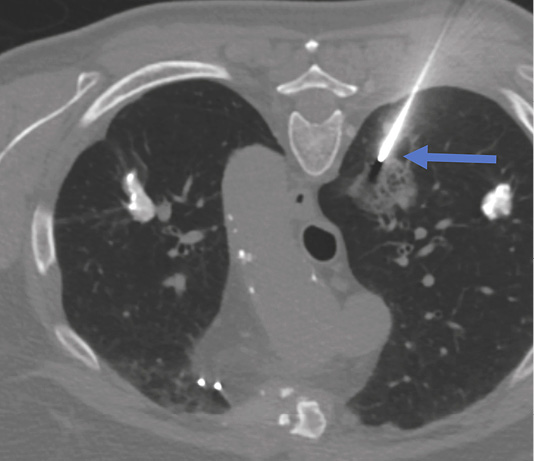

Figure 2. Biopsy of the right lung lesion. Coaxial needle punctured peripheral area of the lesion (blue arrow). Patient is in prone position during the biopsy.

Lung biopsy procedure was performed under local anesthesia in a prone position and the patient was instructed of shallow breathing. 17 gauge coaxial needle was inserted under CT guidance and proceeded up to the lung needle while lung biopsy was performed with 18 gauge needle with automated biopsy gun (Figure 2) sampling two biopsy specimen cores.